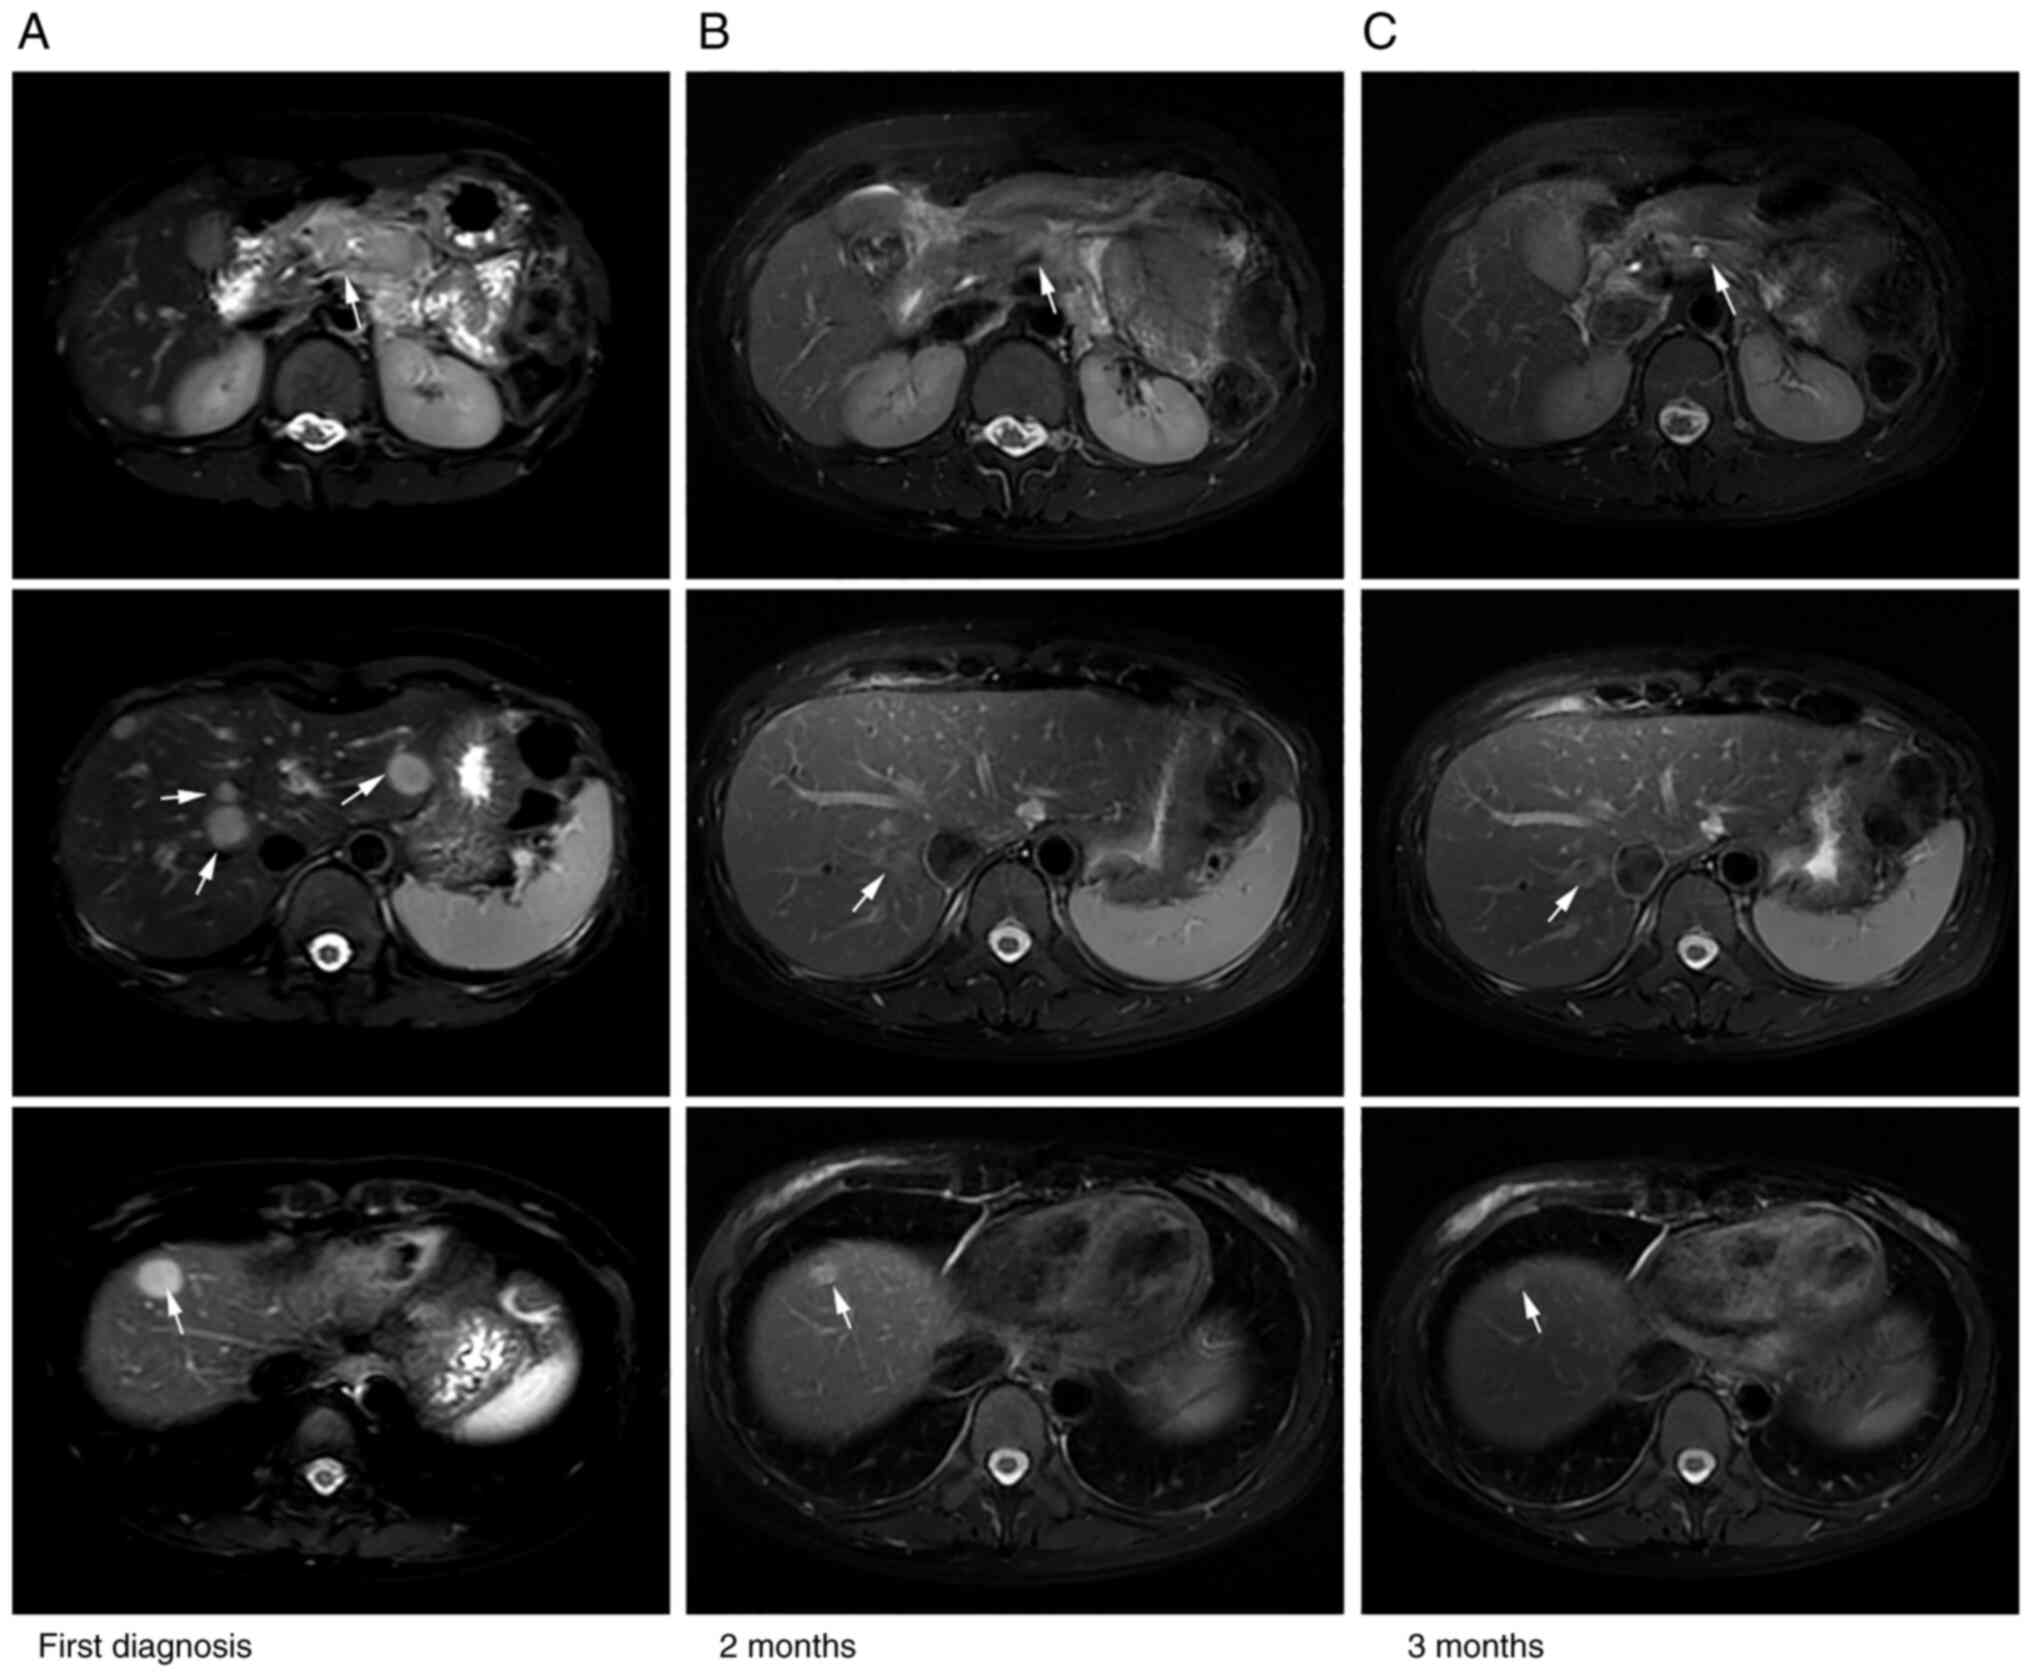

A 42-year-old woman presented with increased levels of serum tumor markers, including carbohydrate antigen (CA)19-9 (3,793 U/ml; normal range, 0–27 U/ml) and carcinoembryonic antigen (CEA; 58.6 ng/ml; normal range, 0–4.7 ng/ml), during a routine physical examination in June 2020, with no obvious symptoms. Enhanced MRI in Renji Hospital (Shanghai, China) 5 days later revealed a mass (49×26 mm) in the pancreatic body and multiple hepatic lesions (Fig. 1A). Next, MRI-guided biopsy of the pancreatic tumor was performed, following which somatic adenocarcinoma of the pancreas was diagnosed. The staging was cT3NxM1, stage IV according to the 8th edition of the American Joint Committee on Cancer for Pancreas and Hepatobiliary Cancers (9). Therefore, the patient was eligible to take part in a single-arm clinical trial assessing the combination of doublet chemotherapy [nab-paclitaxel and gemcitabine (AG)] and the novel PD-1 inhibitor camrelizumab (formerly SHR-1210) for the first-line treatment of metastatic pancreatic carcinoma (ClinicalTrials.gov identifier: NCT04181645; Table I). Therefore, the patient was prescribed first-line immunotherapy treatment of AG + anti-PD-1 immunotherapy 2 weeks after admission for six cycles. The regimen included nab-paclitaxel (Abraxane; 125 mg/m2) and gemcitabine (1,000 mg/m2) on days 1 and 8, along with camrelizumab (200 mg) on day 1 every 3 weeks. Repeat imaging assessment after two and four cycles of this combination treatment revealed a significant reduction in the size of the pancreatic and liver lesions (Fig. 1B). In addition, subsequent MRI scans (Fig. 1C) showed further shrinkage of the tumor and partial response (PR) was concluded using the modified Response Evaluation Criteria in Solid Tumors assessment criteria (Fig. 1) (10). The tumor markers CA19-9 and CEA were restored to the normal ranges. According to the Common Terminology Criteria for Adverse Events (version 4.03) (11), adverse events occurred, which included grade 1–2 rash, edema of the bilateral ankles and eyelids, knee pain, hyperhidrosis and grade 1 anemia. However, no treatment-related grade 3 or 4 adverse events were observed. The patient was next administered six cycles of first-line anti-PD-1 immune maintenance therapy (200 mg camrelizumab on day 1 every 3 weeks) 4 months after admission. After two cycles, a continuous PR was obtained. After the fourth cycle, the pancreatic mass increased slightly in size, and the PR of the liver lesions persisted. The toxicity parameter of transient hyperthyroidism appeared during this period. Afterwards, hypothyroidism was detected, which was controlled by supplementation with levothyroxine sodium tablets (100 µg every day). The progression-free survival (PFS) time from this first-line therapy was 9 months.

Figure 1.

Comparison of abdominal MRI before and after the first-line treatment. MRI images from (A) the time of admission and after first-line treatment at (B) 2 and (C) 3 months post-diagnosis. The pancreatic mass and liver metastases were reduced in size after treatment. Arrows indicate the tumors and lesions.